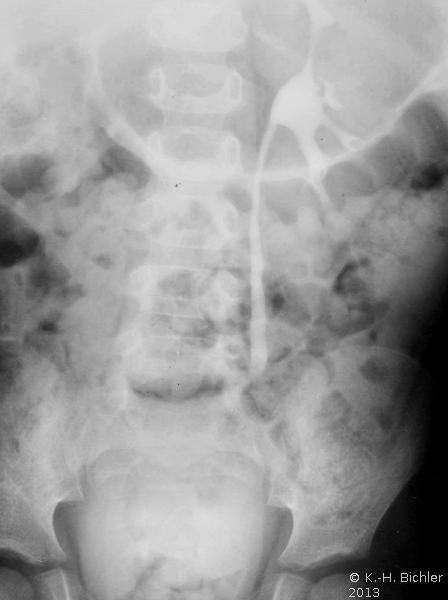

Sie tritt zumeist bei Patienten mit Diabetes Mellitus bzw. bei Harnwegsobstruktionen auf (Komplizierte Pyelonephritis). Dabei können eine oder alle Papillen befallen sein. Histologisch findet sich eine koagolative Infarktnekrose, d.h. die Umrisse von befallenen Tubuli sind erhalten. Leukozytäre Reaktionen finden sich an den Rändern der Nekrosebezirke Literatur:Robbins: "Pathologic Basis of Disease", Saunders Philadelphia, 1999.